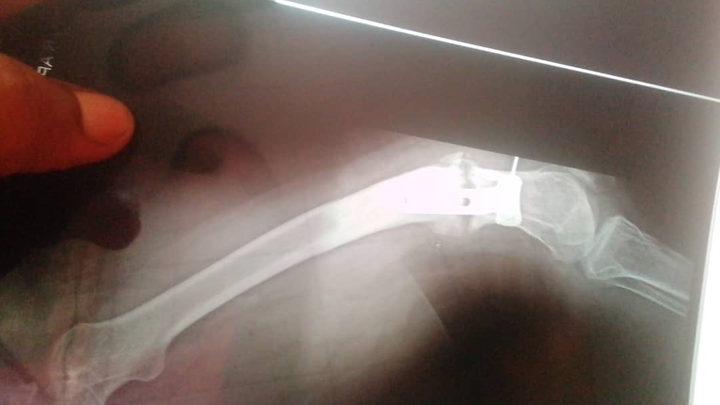

For years, I suffered in silence, unable to get proper care. Eventually, I returned to my mother’s home and began to rebuild my life. However, the pain remained, and in 2021, it intensified. To my shock, I learned that an iron implant had been in my leg for 15 years without my knowledge.

Recently, I had another surgery, thanks to the support of a wonderful woman named Mum Shantal. Unfortunately, the procedure did not go as planned. The surgeon was supposed to straighten my bent leg, but they failed to properly lock the bone in place. As a result, I am now in even more pain, and my condition is worse than before.

I visited another hospital for a second opinion, where a doctor explained that the previous surgery was done incorrectly. I need a complex and crucial operation to correct the mistakes, which involves removing bone from my waist and inserting it into my leg. This is the only option for my body to support my leg properly and alleviate the constant pain.